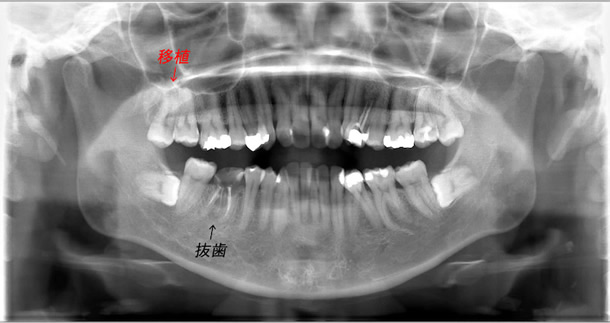

| 右下の親知らずが手前の歯(第二大臼歯)に倒れ込んでることが原因で骨縁下に虫歯ができてしまった。また根尖病巣も認められるため後ろの親知らずを手前に移植した。 | ||